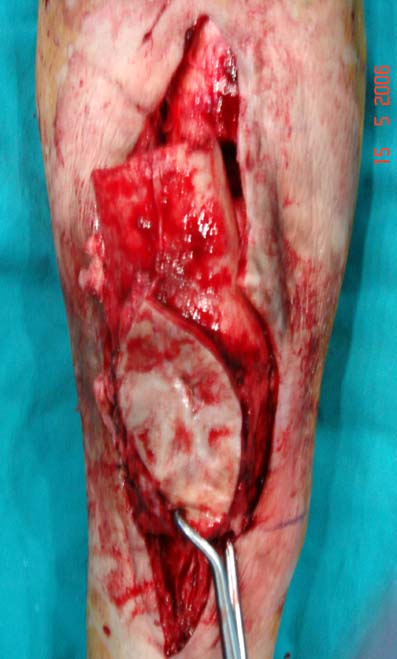

Kronik osteomiyelit, kemik ve yumuşak dokularda nekroza yol açar. Ölü kemik, patojen mikroorganizmalara ev sahipliği yapan bir nidus oluşturur. Konağın savunma sistemleri, mikroorganizmalarla baş etmek için sıklıkla optimal koşullarda değildir. Dolaşım bozukluğu yüzünden enfeksiyon bölgesine antibiyotikler yeterince ulaşamaz. Bu nedenle ölü dokuların ortamdan tamamen uzaklaştırılması gerekir (radikal debridman).

Uygun radikal debridman tüm nekrotik kemik ve yumuşak dokuların çıkartılmasını gerektirir, ve sıklıkla uzuvda instabiliteye neden olur. Kalan kemik ve yumuşak doku defektinin bir şekilde fiksasyonu ve rekonstrüksiyonu gereklidir. İlizarov’un ortaya koyduğu distraksiyon osteogenezi yöntemi, kaynamanın elde edilmesi, deformitenin düzeltilmesi, bacak boy eşitsizliğinin giderilmesi ve segmental defektlerin rekonstrükte edilmesi için başarıyla kullanılmaktadır.